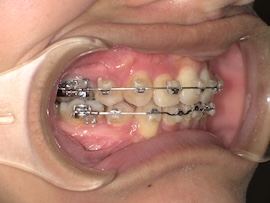

前回から1ヶ月後の歯並びはこんな感じです。

左上親知らずの牽引を始めてたった1ヶ月ですが、かなり出てきている気がします。

内側の装置は汚れが溜まりやすいのか前歯との間の歯肉が腫れ痛みが出ることが時々ありました。話しづらさ等の違和感はもう全くありません。